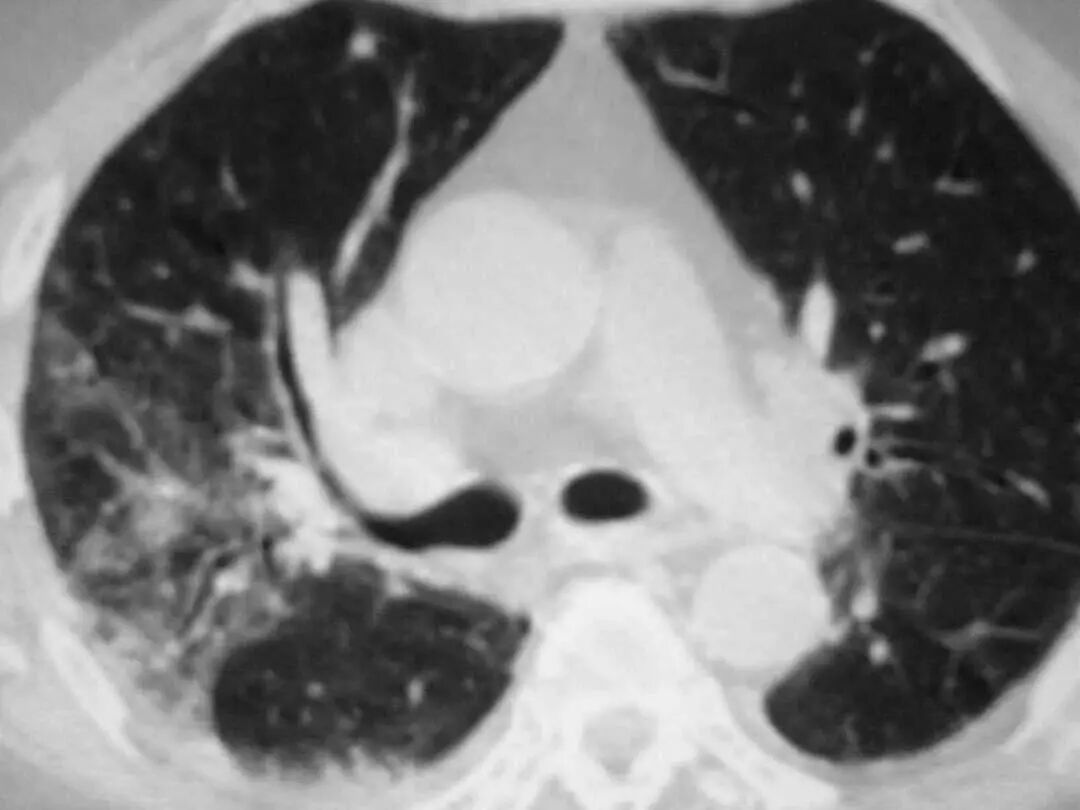

图1.7 CT扫描显示左下叶模糊的气腔浸润。